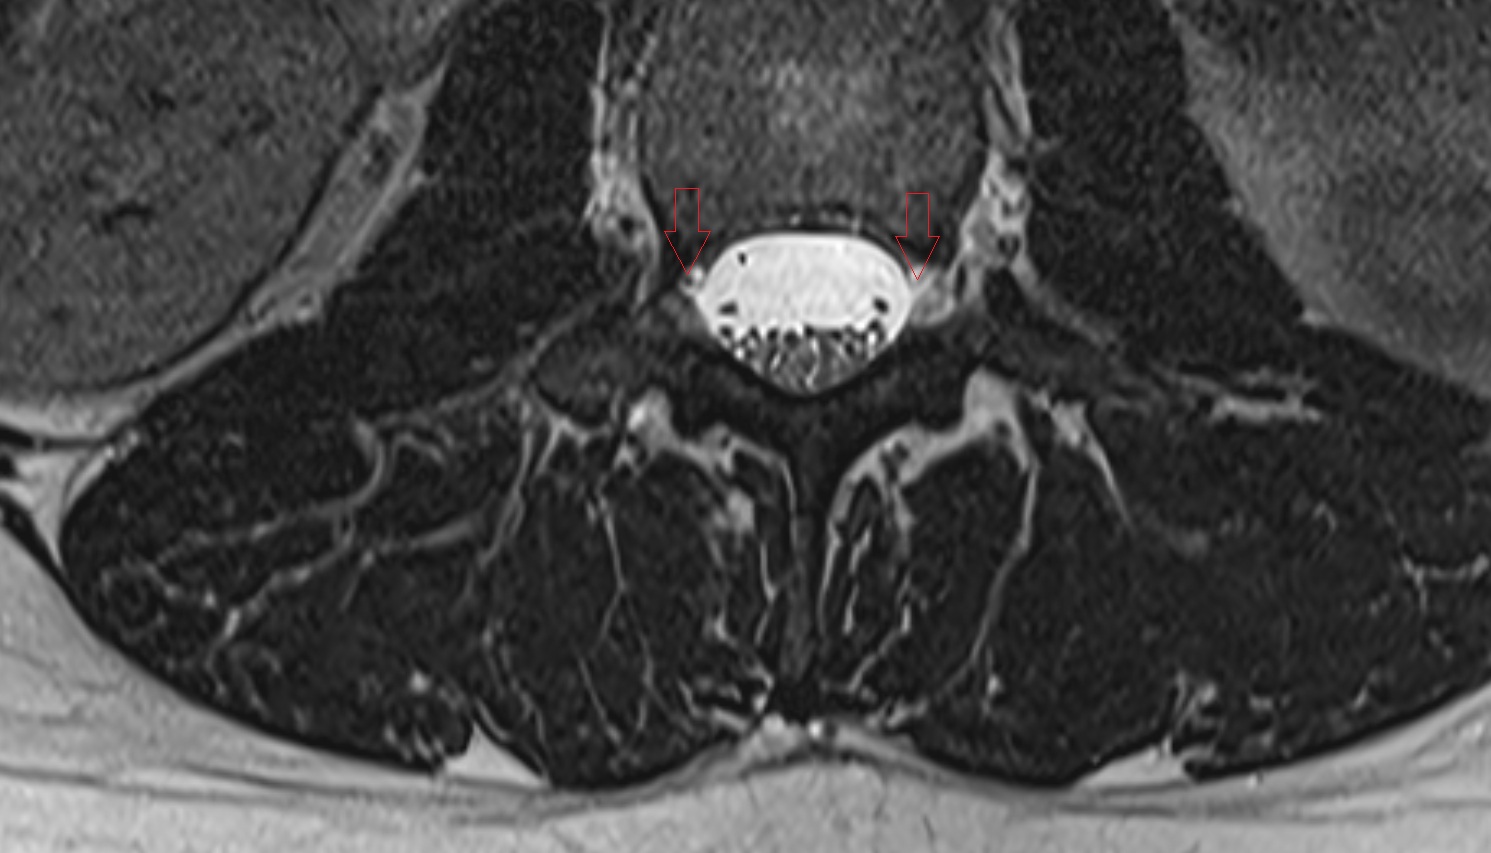

- Traversing nerve root of spinal nerve

- Exiting nerve root of spinal nerve

- Spinal dura mater

- Spinal epidural space

- Dorsal traversing nerve root

- Ventral traversing nerve root

- Dorsal exiting nerve root

- Ventral exiting nerve root

- Dorsal root ganglion of spinal nerve